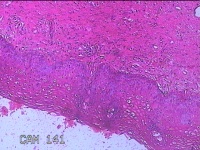

宫颈9点组织

性别

女

年龄

50岁

临床诊断

宫颈上皮内肿瘤?

一般病史

HPV68阳性持续感染1年。

标本名称

大体所见

灰白粉红色组织0.3x0.2x0.1cm一块,表面光滑。